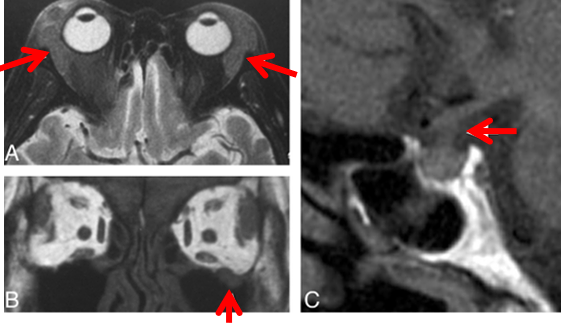

眼附属器受累

(图片均来源文末参考文献)

泪腺受累